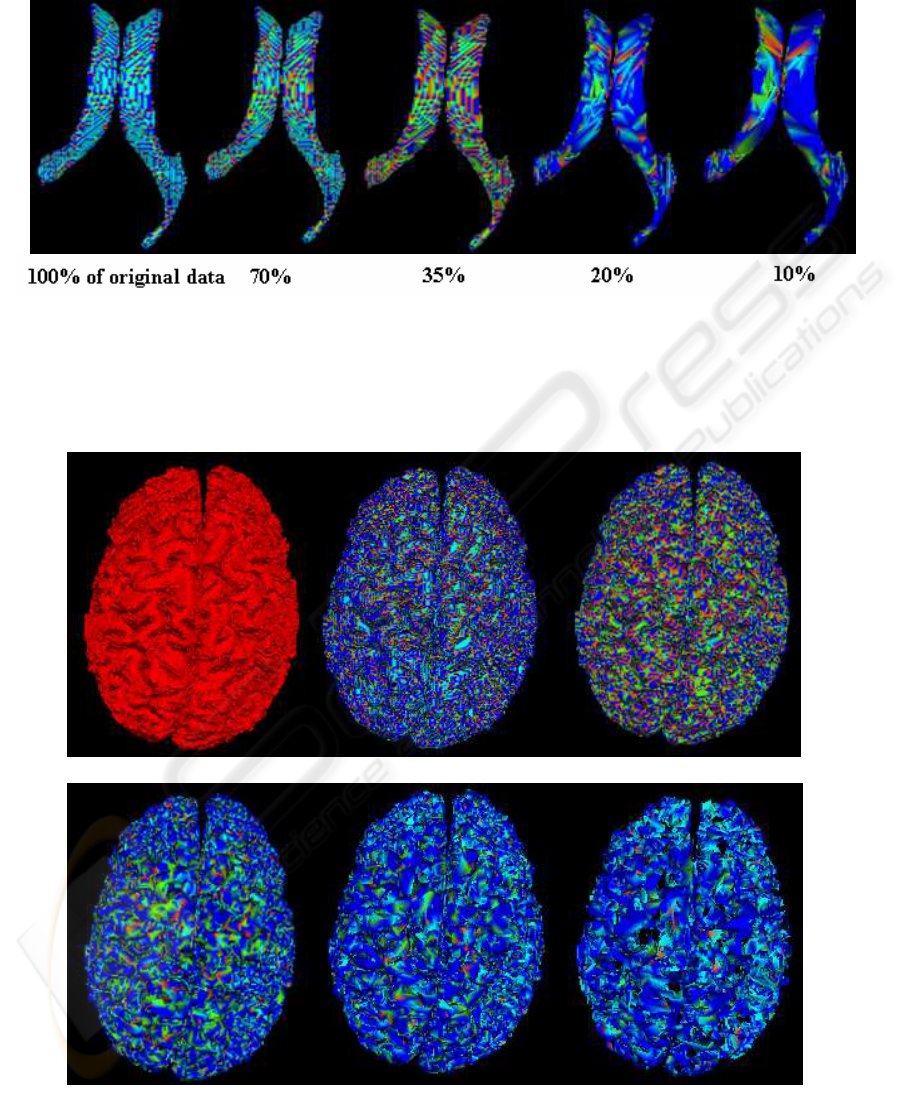

corresponds to a different color in all obtained res-

olutions. According to these results, we notice that

segmentation at low-resolution (10% of the original

data) leads to an extraction of the major surface fea-

tures/characteristics, whereas when the algorithm is

applied to the surface at high resolution (100%), it

does not necessary produces more relevant structure

information but includes small features, which do not

contribute very much to the overall shape. In addi-

tion, low-resolution description can be used to deter-

mine constraints for the segmentation at higher reso-

lution. For instance, these first results are encourag-

ing but further investigation is required to extend the

algorithm to a large range of data.

Figure 6: Segmentation of the cortical surface according to

table 1.